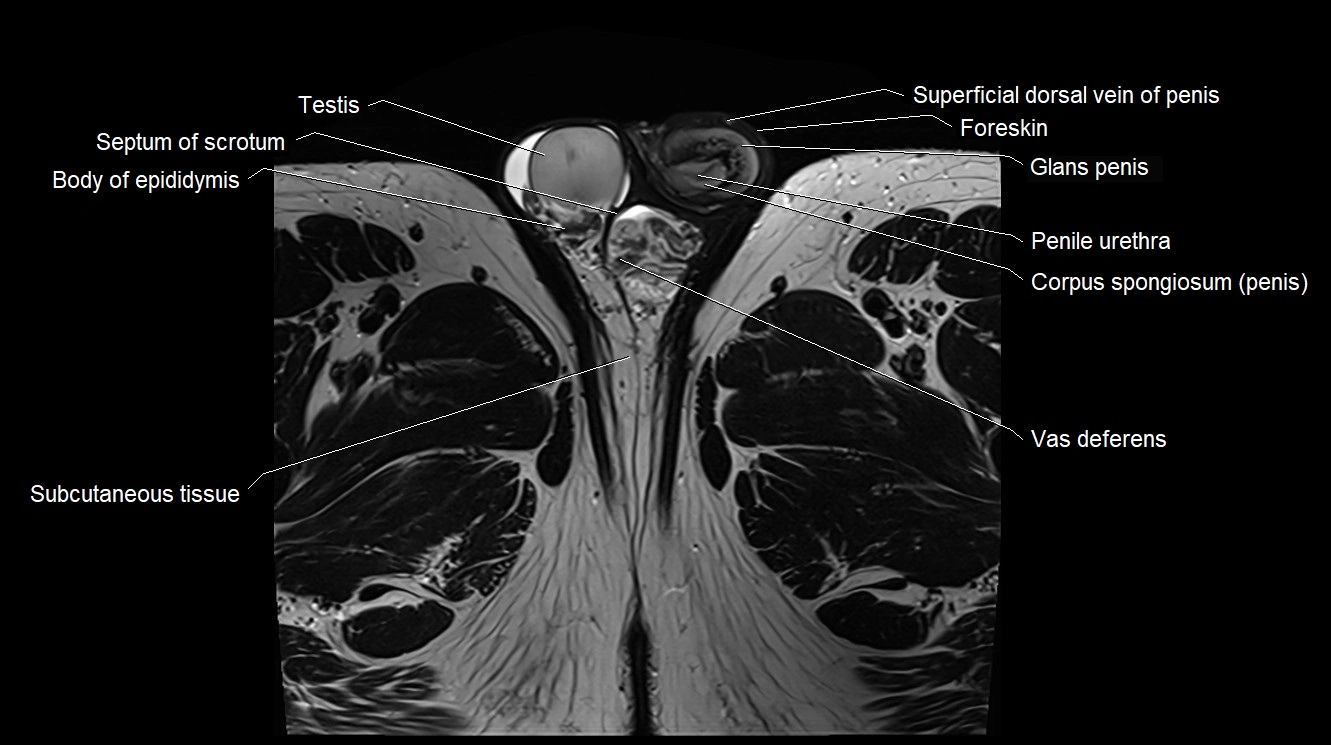

- Body of epididymis

- Penile urethra

- Septum of scrotum

- Subcutaneous tissue (scrotum)

- Superficial dorsal vein of penis

- Testis

- Vas deferens